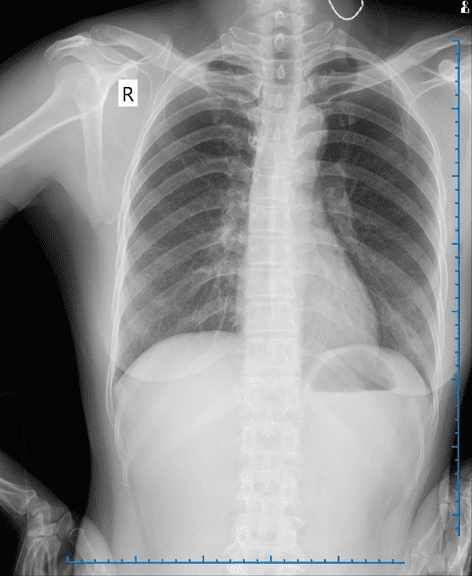

Qua các bước khám lâm sàng và cận lâm sàng chuyên sâu, các bác sĩ xác định vùng cổ bệnh nhân có một khối u kích thước 3x3 cm. Khối u có mật độ mềm, di động tốt, vùng da xung quanh không có dấu hiệu viêm nhiễm.

Phim chụp X-Quang của bệnh nhân